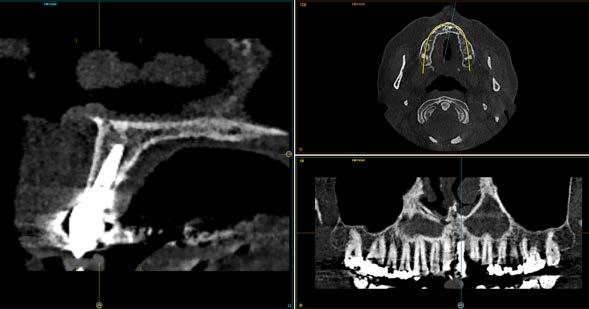

Figuras 1 y 2. Imágenes iniciales de la paciente. Se observa el diente en posición 21 con un cambio de color evidente y supuración espontánea a través del surco gingival. Asimismo, se aprecia el impacto estético del cambio cromático en la sonrisa y en el aspecto del frente anterosuperior.

Figura 3. Radiografía de la zona que muestra el tratamiento previo de apiconformación realizado en el incisivo para lograr el cierre apical, actualmente fracasado. Se observa además una lesión quística asociada al ápice.

El caso clínico que se presenta en este artículo ejemplifica la aplicación de estas estrategias en un paciente rehabilitado con implantes tras la extracción dentaria y la regeneración temprana del alveolo con PRGF-Endoret, combinando la sobrecorrección vestibular mediante hueso particulado y el uso de biomateriales autólogos. La relevancia de este caso radica en el extenso seguimiento clínico y radiográfico de 22 años, que ofrece una oportunidad excepcional para valorar la estabilidad funcional, estética y tisular del tratamiento a muy largo plazo.

Caso clínico

Se presenta el caso de una paciente femenina de 47 años de edad al inicio del tratamiento, quien acude a consulta por dolor y supuración en el incisivo central superior izquierdo. En las imágenes iniciales se observa un diente con un cambio de color llamativo y una supuración espontánea a través del surco gingival (Figura 1). Esta alteración cromática, además de reflejar un problema asociado al diente, afecta de manera significativa la estética del frente anterior, como se aprecia en la imagen de sonrisa (Figura 2).

El diente había sufrido un traumatismo durante la infancia de la paciente y, tras la pérdida de vitalidad pulpar,

Rehabilitación de incisivo central con implante diferido y sobrecorrección con injerto óseo particulado y PRGF-Endoret

se realizó un tratamiento de apiconformación que, al momento de la revisión, mostraba signos de fracaso, con evidencia de infección y clínica sugestiva de fractura radicular (Figura 3).

Como primera fase del tratamiento, se procedió a la exodoncia del diente y a la regeneración del alveolo con PRGF-Endoret, tras un legrado minucioso del lecho. Una vez completada esta regeneración, a las 14 semanas

se llevó a cabo la fase quirúrgica para la colocación del implante.

Se elevó un colgajo a espesor total con márgenes amplios (Figuras 4 y 5), lo que permitió recolectar hueso autógeno de las áreas adyacentes mediante un rascador óseo. Este abordaje facilitó además un cierre primario sin tensión tras la colocación del implante y la sobrecorrección. El hueso obtenido se mantuvo en PRGF-Endoret,

Figuras 4 y 5. Elevación del colgajo, donde se aprecia el lecho alveolar regenerado y la zona donante situada por encima del ápice del diente 11.

fracción 2 sin activar, hasta el momento de su utilización en la zona receptora, preservando la vitalidad celular y mejorando la manejabilidad del injerto particulado (Figura 6). Posteriormente, este hueso se unió al recolectado durante el fresado biológico del lecho.10

El lecho implantario se preparó mediante fresado biológico, ajustado al tipo de hueso y a las dimensiones del implante planificado. A continuación, se procedió a la inserción del implante, que alcanzó un torque de inserción adecuado, permitiendo dejarlo en fase de cicatrización con el pilar

correspondiente colocado. Una vez colocado el implante y el pilar de cicatrización, se realizó una técnica de sobrecorrección vestibular con el injerto particulado inmerso en PRGF-Endoret, recubriendo toda la zona con una membrana autóloga de fibrina (fracción 1 activada y retraída). Se suturó con monofilamento no reabsorbible, sin tensión, para evitar el colapso del volumen vestibular que se buscaba ganar (Figuras 7 a 10). Como provisional se empleó el propio diente de la paciente, ferulizado a los adyacentes con resina, a modo de puente Maryland (Figura 11).

Tras 6 meses de oseointegración, se procedió a la confección de la prótesis definitiva. En aquel momento, hace 22 años, se eligió un biopilar microfresado y una corona metal-cerámica cementada, que representaban la mejor alternativa para garantizar un sellado adecuado y una estética satisfactoria en el sector anterior. En la actualidad, la opción preferible habría sido una prótesis atornillada con un elemento intermedio (transepitelial unitario) y una corona totalmente cerámica cementada a una interfase. No obstante, es importante contextualizar la decisión en función de la época en la que se finalizó el caso (Figuras 12 y 13).

La paciente ha permanecido en seguimiento y mantenimiento clínico durante 22 años, sin evidenciarse pérdidas óseas periimplantarias ni recesión gingival en torno al perfil de emergencia (Figura 14). En la actualidad, se realizó

Figura 6. Hueso autólogo obtenido mediante fresado y rascado de las zonas adyacentes, embebido en PRGF-Endoret fracción 2 sin activar hasta el momento de su utilización.

Figuras 7 y 8. Colocación del implante y sobrecorrección vestibular con injerto particulado embebido en PRGF-Endoret, una vez posicionado el pilar de cicatrización.

un cone beam de control para valorar el estado de un tratamiento endodóntico en la pieza 26; en el corte seccional correspondiente al implante se aprecia una estabilidad completa, con un volumen vestibular óseo significativo.

Estos hallazgos confirman el éxito del procedimiento quirúrgico y de la posterior carga progresiva, con un mantenimiento óptimo de los tejidos duros y blandos a lo largo de más de dos décadas (Figura 15). Los cambios entre el momento inicial y el final del tratamiento son evidentes, especialmente al comparar la imagen intraoral de la primera visita con la tomada a los 22 años, donde la mucosa que rodea al diente 21 —y posteriormente al implante— se muestra engrosada, en buen estado de salud y con una estética destacable. Asimismo, la comparación entre la radiografía inicial, que evidenciaba el fracaso del tratamiento de conductos del diente en posición 21, y la radiografía a los 22 años, que muestra el implante sin pérdidas óseas asociadas, resulta elocuente (Figuras 16 a 19).